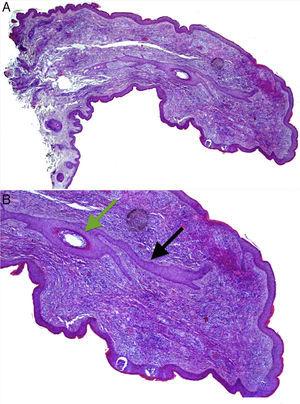

Both lesions were excised. Histological examination of the papule from the left alar rim was compatible with a vascular hamartoma. The lesion from the columella showed features compatible with a fibrofolliculoma (Fig. 2A and B).

(A) Histopathology of the papule located on the columella. Hematoxylin and eosin, original magnification 20×. (B) A central hair follicle (green arrow) with anastomosing bands of follicular epithelium extending from the central hair follicle into the adjacent stroma (black arrows), compatible with a fibrofolliculoma. Hematoxylin and eosin, original magnification 100×.